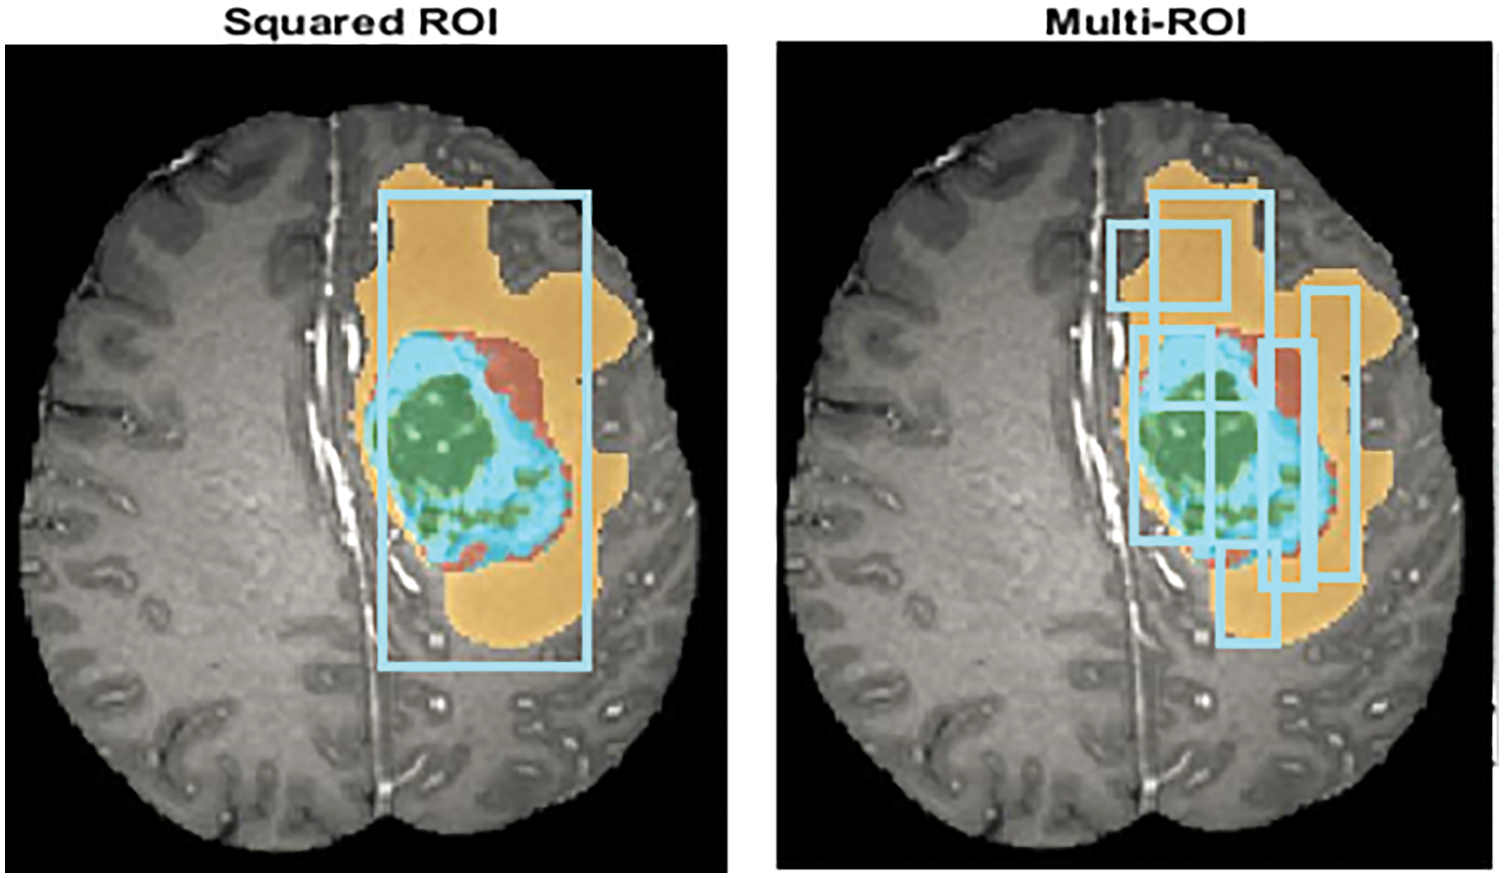

The segmentation technique rationally distributes the image into different parts to better understand the semantics of an image. This technique is helpful for the image dataset at the preprocessing stage to detect the identical region of interest (ROI), as shown in Fig. 2. These techniques extract the areas of the high intensity to get better quality of the brain tumor affected regions. The region-based segmentation of brain tumor images extracts only the affected areas in terms of multiple ROIs [52].

Figure 2: ROI feature extraction